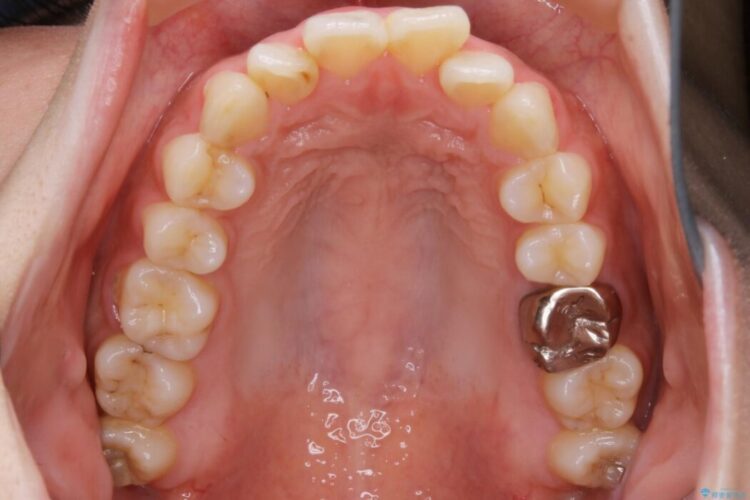

口ゴボに加えて歯列のガタガタを改善したいと来院されました。

患者様のご希望によりインビザライン装置での治療を行いました。

インビザラインは歯を後ろへ動かす動き、非抜歯での矯正治療が得意なため、ワイヤー装置では難しいケースでも対応できる場合があります。